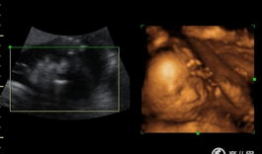

四维视频,四维视频揭秘未知世界

哇,你有没有想过,未来看电影会是什么样子?想象你戴上眼镜,眼前不再是平面的画面,而是一个立体的世界,仿佛你真的置身其中。这就是四...

2025-11-24 179 -